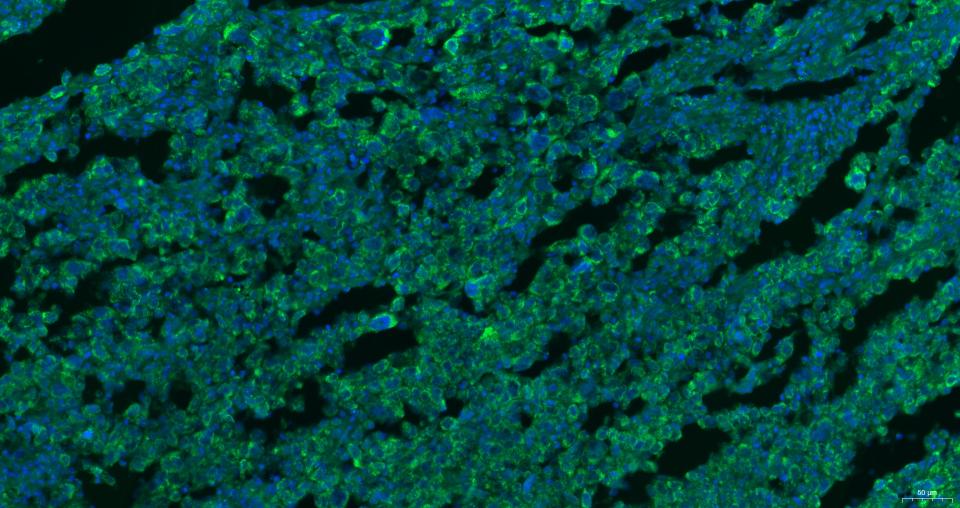

| IF | Human, Mouse, Rat | 1:100-500 |